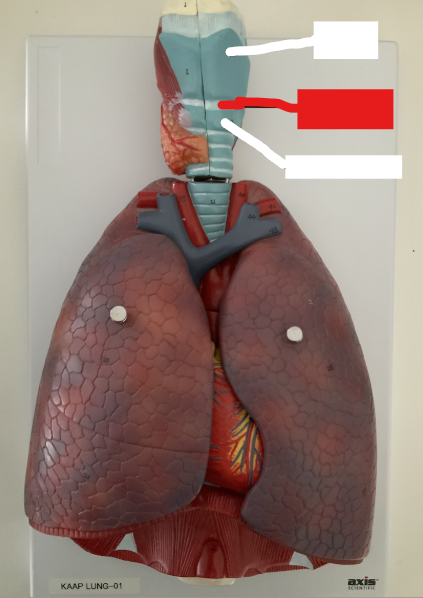

What structure is this?

Diaphragm

What structure is this?

Hard Palate

What structure is this?

Soft Palate

What structure is this?

Uvula

What structure is this?

Thyroid Cartilage

What structure is this?

Cricothyroid Ligament

Cricoid Cartilage

What structure is this?

Epiglottis

What structure is this?

Trachea

What structure is this?

Tracheal Cartilage